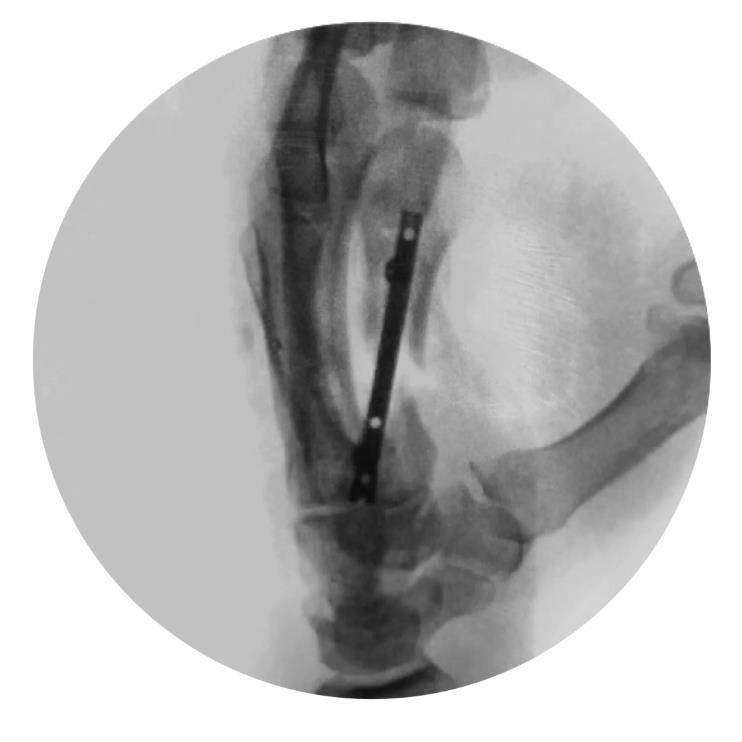

Locking Hand Nail System

• The Locking Hand Nail System from Skeletal Dynamics is an intramedullary fixation system designed for the stabilization of fractures of the metacarpals and proximal phalanges

• The device provides minimally invasive internal fixation through a headless, cannulated nail that is inserted within the medullary canal to maintain fracture alignment while minimizing soft-tissue disruption

• The system incorporates distal locking screw options to enhance rotational and axial stability, allowing controlled fixation of extra-articular fracture patterns

• The Locking Hand Nail System is part of a specialized hand fracture fixation platform and includes multiple nail diameters and lengths, dedicated instrumentation, and compatible locking screws to accommodate variations in hand anatomy and fracture configuration

• Metacarpal

• nails can be introduced either in an antegrade or retrograde direction

• the illustrated surgical technique uses an antegrade approach